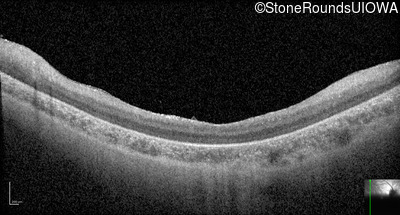

Optical Coherence Tomography - Left - 10/350 sc

Exemplar / OCT Stack